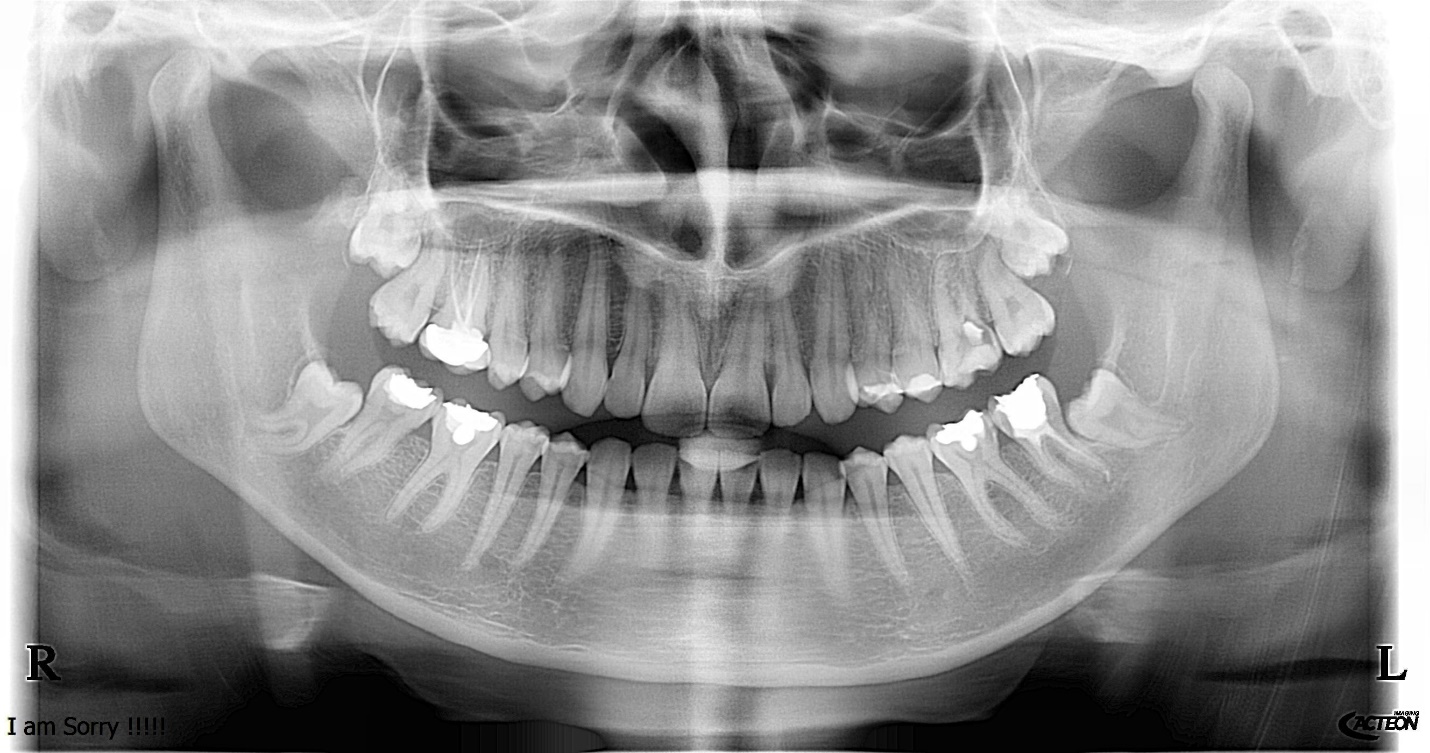

Figure 6. This Panoramic X-ray showed signs of a low risk of nerve injury.